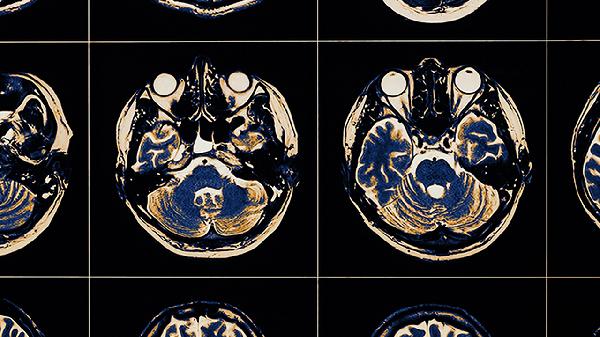

脑干或下丘脑病变可能直接影响睡眠觉醒中枢,需进行头颅MRI或CT检查。阿尔茨海默病等神经退行性疾病早期可能出现昼夜节律紊乱,伴随认知功能下降症状。自主神经功能失调患者常伴有心率变异率异常,可通过相关检测辅助诊断。